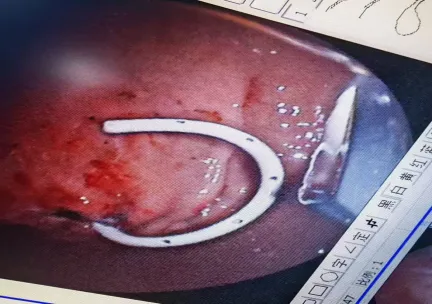

置入双猪尾塑料支架

支架植入后可见胰腺假性囊肿囊液及坏死物质引流出

这根支架在囊肿和胃腔之间搭起一座“桥梁”,将胰腺假性囊肿囊液及坏死物质引流至消化道,随之排出体外。整个过程严格遵循“EUS引导穿刺-置入导丝-针状刀切开-扩张窦道-置入双猪尾塑料支架”的标准化流程,精准建立引流通道。整个手术无需在体表制造任何切口,实现了真正的“超级微创”。